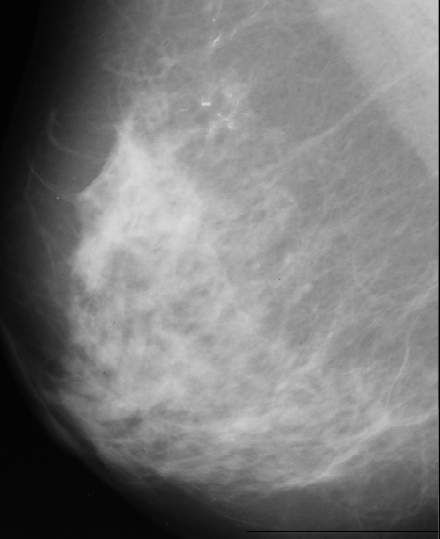

There are many black pixels, and few bright pixels. The selected threshold is at the first position in the histogram where the difference between two consecutive positions is smaller then a given value. After that we eliminate the shapes with areas bigger than given threshold. The result of this approach is presented bellow:

Figure 3.

As we can see this approach is very noisy, contain many false-positives.